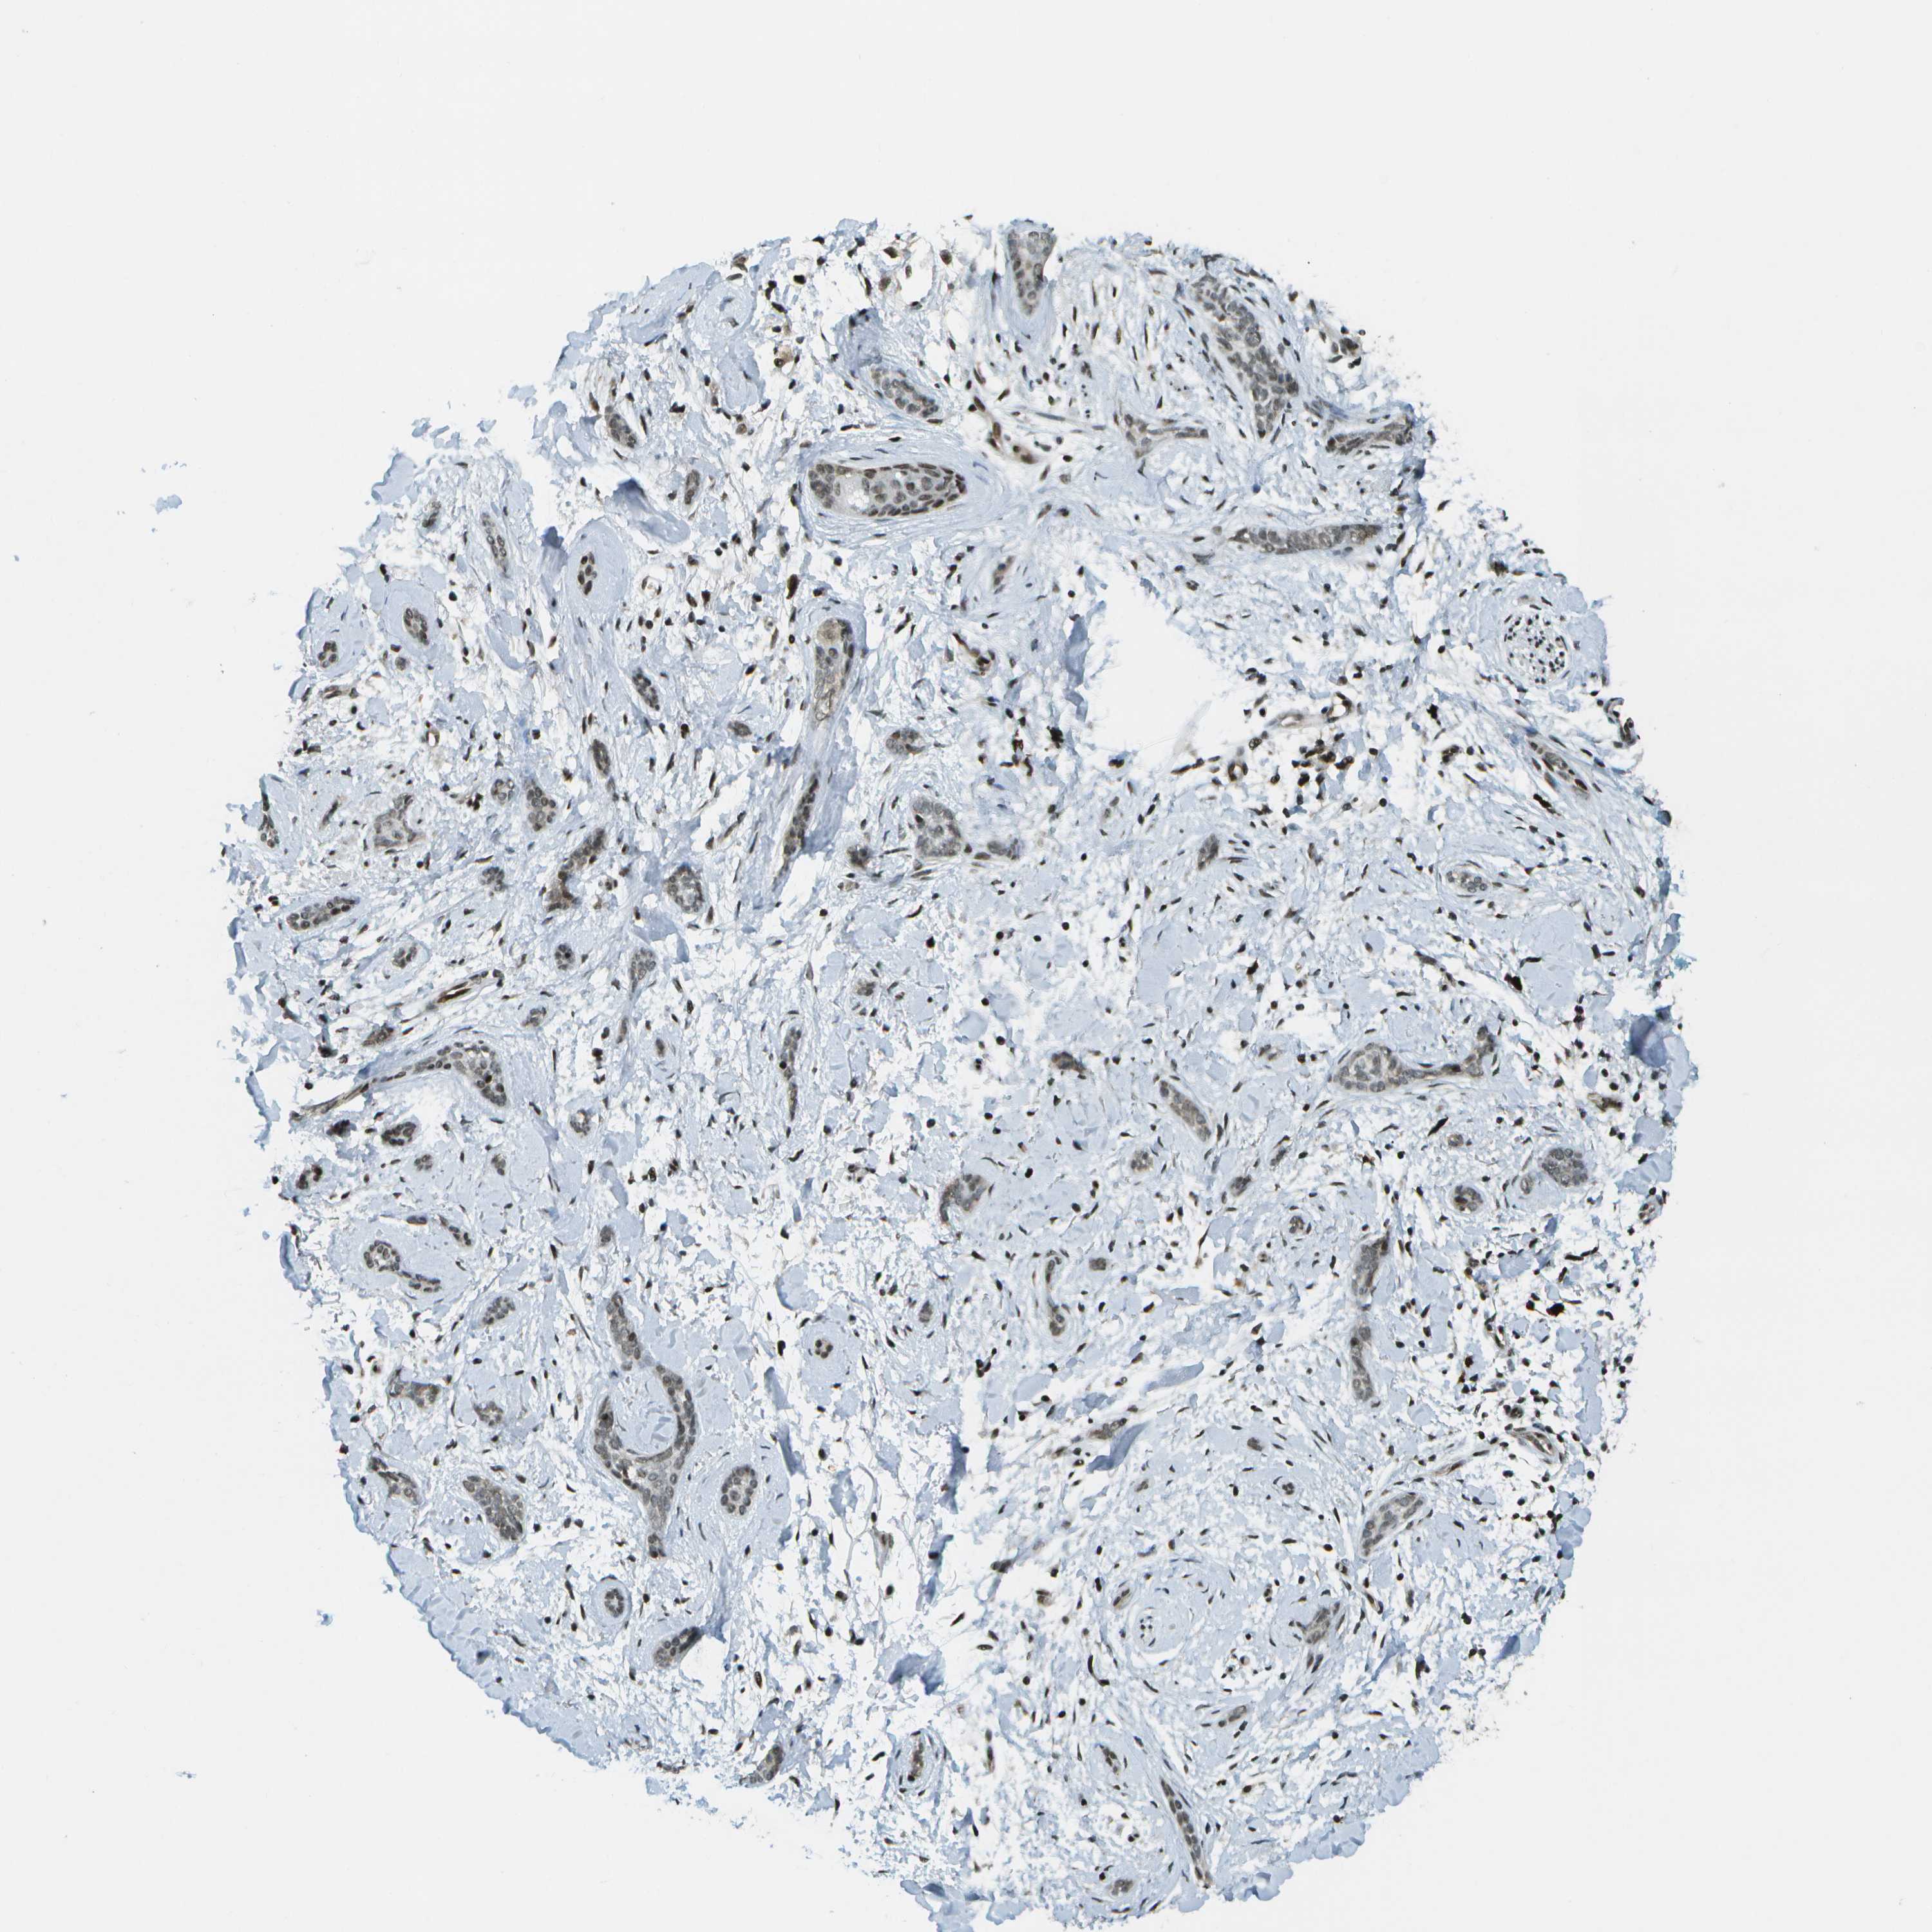

SKIN CANCER - Protein expressioni

A mouse-over function shows sample information and annotation data. Click on an image to view it in a full screen mode. Samples can be filtered based on level of antibody staining by selecting one or several of the following categories: high, medium, low and not detected. The assay and annotation is described here.

Antibody stainingi

Antibody staining in the annotated cell types in the current human tissue is reported as not detected, low, medium, or high, based on conventional immunohistochemistry profiling in selected tissues. This score is based on the combination of the staining intensity and fraction of stained cells.

Each image is clickable and will lead to virtual microscopy that enables deeper exploration of all samples and also displays staining intensity scores, fraction scores and subcellular localization as well as patient and tissue information for each sample.

Antibody CAB017694

Squamous cell carcinoma, NOS